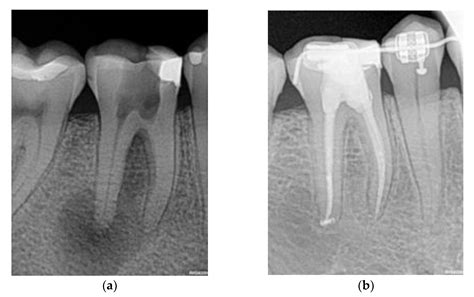

1. Diagnosis and Anesthesia: Your dentist will take X-rays to assess the extent of the infection. Local anesthesia is administered to ensure you do not feel pain during the treatment.

3. Cleaning and Shaping: The infected pulp is carefully removed using specialized dental instruments. The canals are then cleaned, disinfected, and shaped to receive a filling material.

4. Filling and Sealing: The hollowed-out canals are filled with a biocompatible material called gutta-percha, which is cemented into place.

5. Restoration: Because a tooth that has undergone an Rct of teeth may become brittle, a crown or permanent filling is usually placed to protect it and restore its original functionality.